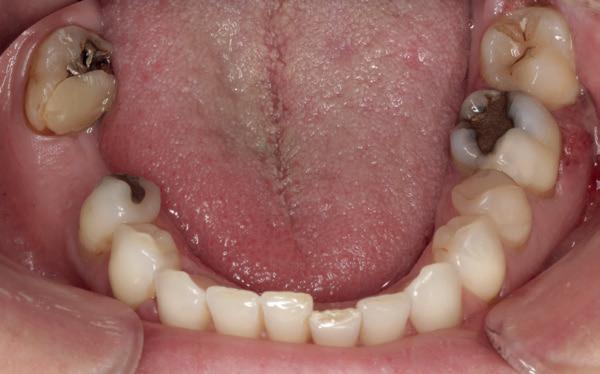

De patiënt werd in de eerste fase gezien door de parodontoloog, implantoloog en restauratief behandelaar. Klinisch werden drie complicerende factoren vastgesteld: inadequate mondhygiëne, een ongunstige occlusale relatie en restauraties met gebrekkige marginale adaptatie met overhang. De patiënt werd opgenomen in het parodontale behandelprotocol.

De diagnose luidde lokaal parodontitis met ernstige furcatie aandoeningen; Stadium IV (vergevorderd); graad C (snel progressief) (afbeelding 7) De elementen die niet te behouden waren, werden geëxtraheerd.

Na afronding van de eerste twee behandelstappen werd parodontale stabiliteit bereikt, zoals waarneembaar op de parodontiumstatus en (röntgen)foto’s (afbeelding 6, 8). De patiënt toonde aantoonbare verbetering in mondhygiëne (afbeelding 4) en bleef gemotiveerd om de behandeling voort te zetten.